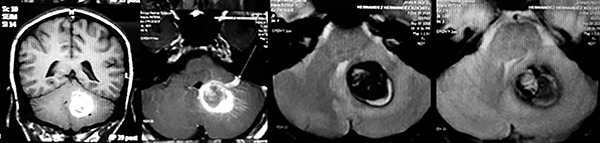

Paciente femenino de 29 años de edad con historial de cefalea crónica que presenta súbitamente disdiadococinesia y dismetría izquierda.

El estudio de RMN presenta una lesión bien circunscrita en hemisferio cerebeloso izquierdo con periferia de predominio hiperintenso en T1 y T2, y centro hipointenso, edema perilesional mínimo, así como una imagen de un vaso venoso alimentador que recorre hacia el ángulo pontocerebeloso izquierdo.

Se realizó una craniectomía suboccipital paramedial derecha, así como un abordaje transcortical en el hemisferio cerebeloso izquierdo llegando a la región perilesional de aspecto amarillento, posteriormente se observa una lesión oscuro-verdoso de contenido hemático antiguo, retirando la cápsula y su contenido en la totalidad.

La evolución clínica de la paciente fue satisfactoria solo preservando la dismetría como secuela.

El resultado histopatológico fue consistente en angioma cavernoso.

El estudio de control de RMN se observa la brecha quirúrgica y ausencia de lesión (figs. 1, 2 y 3).

Lesión cerebelosa izquierda ponderaciones en T1 y T2, la flecha señala vaso nutricio hacia el ángulo pontocerebeloso izquierdo, se puede observar el centro de intensidad heterogénea con contenido quístico multiloculado y edema perilesional leve.

Cortes axiales en ponderación T1, cambios postquirúrgicos.

Paciente masculino de 34 años de edad, quien presenta crisis convulsivas parciales motoras de brazo y hemicara derecha, secundariamente generalizadas, posteriormente hemiparesia 4/5 para hemicuerpo derecho.

La TAC muestra un área hiperdensa a nivel frontal izquierdo heterogénea que no refuerza con medio de contraste.

LA RMN muestra una lesión bien circunscrita frontal parasagital izquierda con edema perilesional, hiperintensa en T1 y T2, de contenido sólido y quístico, con poca captación del medio de contraste.

Se realizó craneotomía frontal para abordaje interhemisférico anterior.

Se realiza resección total de la lesión de contenido hemático oscuro-verdoso, consistente en un angioma cavernoso. La RMN postoperatoria se observa solo la brecha quirúrgica sin evidencia de lesión.

En el postquirúrgico el paciente desarrollo síndrome frontal lateral, que se controló con Risperidona y remitió después de tres semanas, las crisis convulsivas remitieron y el medicamento se disminuyó de manera paulatina (figs. 4 y 5).

Imágenes prequirúrgicas y postquirúrgicas de lesión multiloculada del caso 9.